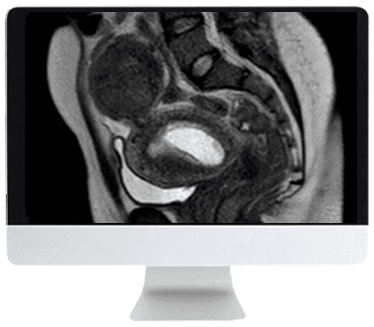

ARRS Abdominal MRI: Practical Applications and Advanced Imaging Techniques 2021 (CME VIDEOS) is a comprehensive online course designed to equip radiologists with practical expertise in advanced MR imaging techniques for abdominal applications. This course covers protocol optimization, standardized interpretive schemas, and specialized imaging strategies for emergency settings and liver MRI, providing an essential resource for enhancing clinical imaging practice.

This course offers detailed modules focused on clinical application and technical advancement in abdominal MRI. Each module includes lectures by experts on key topics such as emergency imaging protocols, liver lesion characterization, protocol optimization, advanced imaging techniques, standardized assessment systems, and case reviews involving gastrointestinal and genitourinary systems.